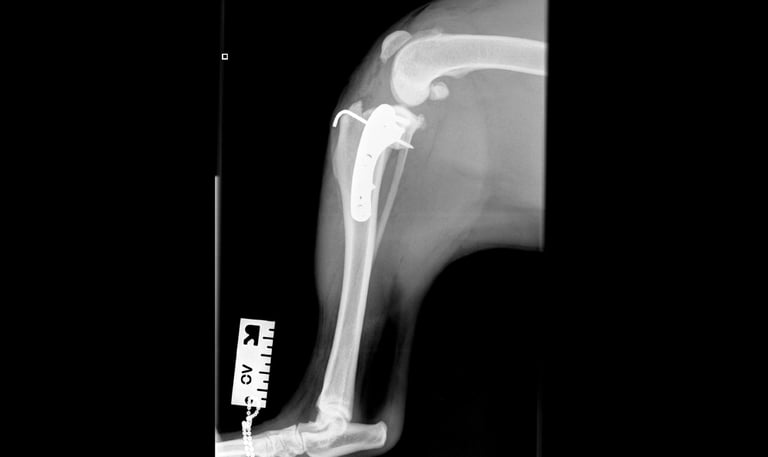

Case 3 - Ralph

Tibial tuberosity avulsion fracture - FBD, 25-week-old, male entire